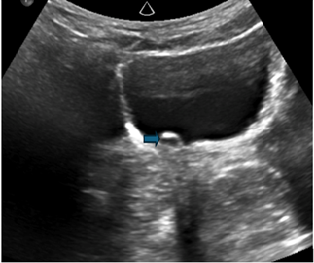

Figure 4: Ultrasound image of the

urinary bladder reveals a prominent right ureter terminating in a ureterocele (

)